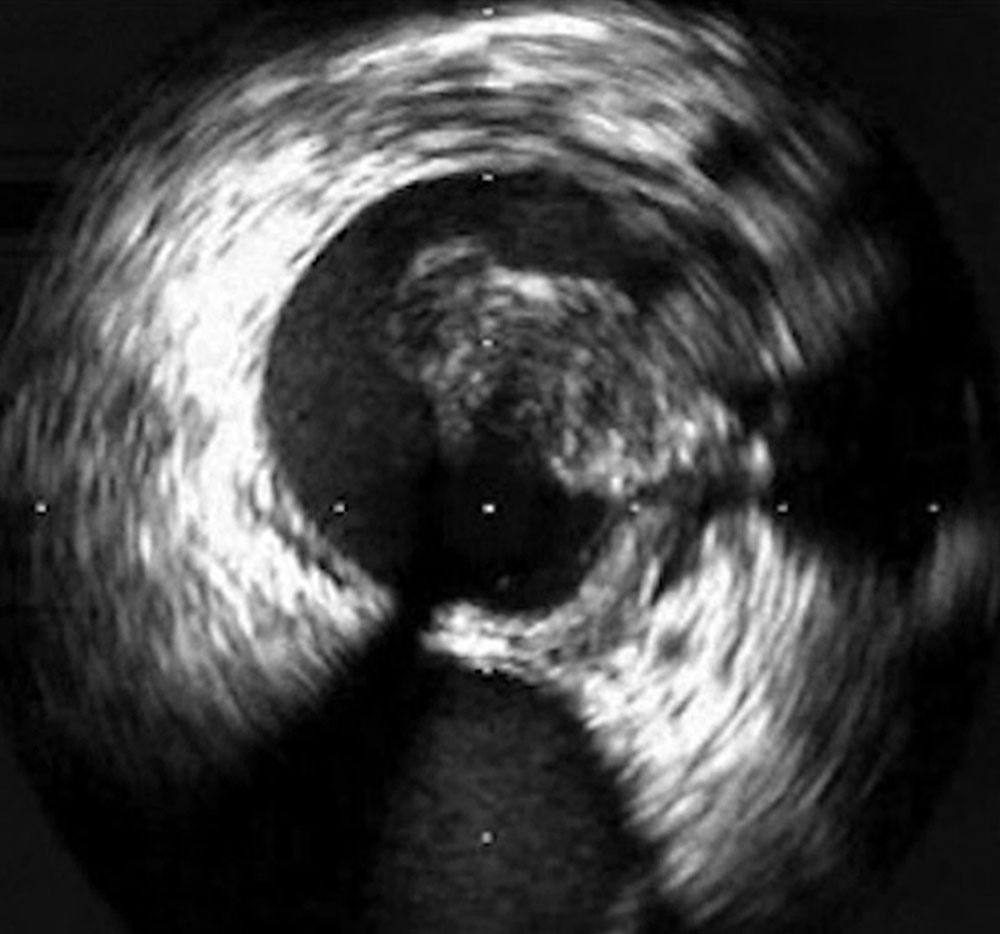

In the case of thrombosis of the central iliac veins, it may be difficult to detect thrombosis by transabdominal sonography because of overlaying structures such as bowel. Phlebography may also produce a false negative in this case. Cross-sectional computed tomography or magnetic resonance imaging may be helpful in such cases if a therapeutic consequence can be derived from it. A good alternative, especially in the area of the proximal common iliac veins, e.g., in May-Thurner syndrome, is intravascular ultrasound, which involves inserting a catheter with an integrated ultrasound probe directly into the vein.